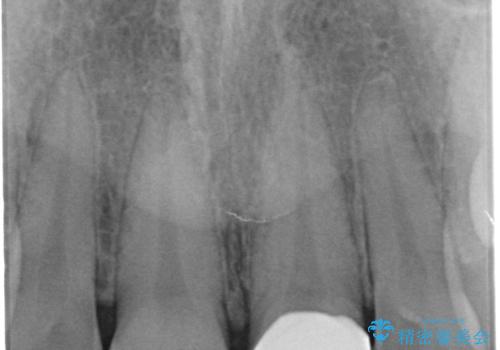

すり減った前歯の形態回復

- すり減ってしまった前歯の審美性の回復を希望され来院されました。

何度かレジン修復を試みたものの、脱離しやすく変色も気になる、とのことでセラミッククラウンによる審美性の回復を計画します。

右側は、クラウンにせず可及的に形態を整えることのみでの対応としました。